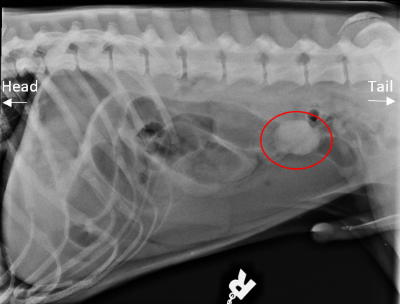

Veterinary Medical and Surgical Group San Juan. Young cats and young large-breed dogs are more likely to present with signs of foreign body obstruction than older animals. Often the foreign body cannot be seen on the x-ray but the consequences of the foreign body obstruction are visible. Clinical signs are variable depending on duration degree and location of the foreign body but often include vomiting and anorexia. Gastrointestinal foreign bodies are an important differential diagnosis for patients presented for vomiting and radiography remains the main initial imaging modality in these cases.

In most cases a veterinarian will assess the dogs condition with X-rays or other imaging scans to determine the safest and most effective approach. Gastric foreign body is a term that refers to any material other than food that is eaten and that results in a serious digestive problem in the stomach. If a foreign body becomes stuck at any point in the digestive tract from the mouth to the esophagus stomach or intestines so that it partially or completely blocks the flow of nutrients and impairs blood flow to the bowel then the foreign body becomes a life-threatening obstruction. The string may cut through the frenulum of the tongue and bury. Often the foreign body cannot be seen on the x-ray but the consequences of the foreign body obstruction are visible.

Young cats and young large-breed dogs are more likely to present with signs of foreign body obstruction than older animals. Several views or a series of specialized X-rays using contrast material barium or other radiographic dye will often be necessary. Black arrows define margins of suspected foreign material. They will pump air into his stomach or make use of Barium to locate any blockage. Often the foreign body cannot be seen on the x-ray but the consequences of the foreign body obstruction are visible.